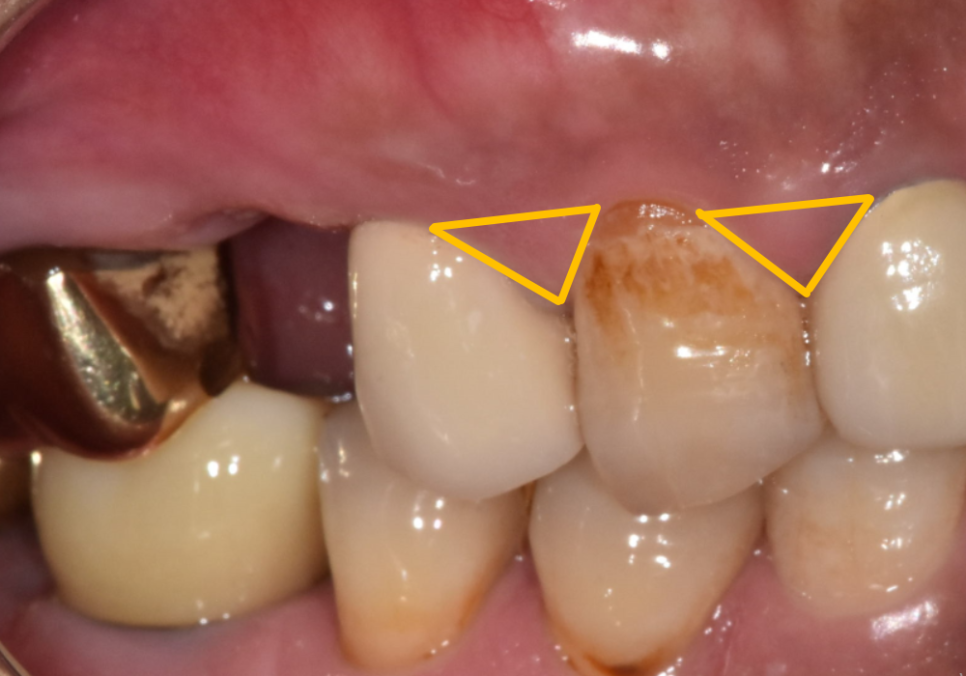

원래 치아 사이에는 이렇게

세모 모양으로 꽉 차 있는 잇몸 살인

치간 유두가 있어서

음식물이 들어오는 걸 막아줍니다.

하지만 치아를 뽑고 나면

이 잇몸 살도 함께 사라지게 되죠.

임플란트를 심은 후에도

이 뾰족한 잇몸은 완벽히 재생되지 않아요.

이로 인해, 치아 사이에

빈 공간이 생기게 되고

이 빈 공간으로 음식물이 끼게 됩니다.